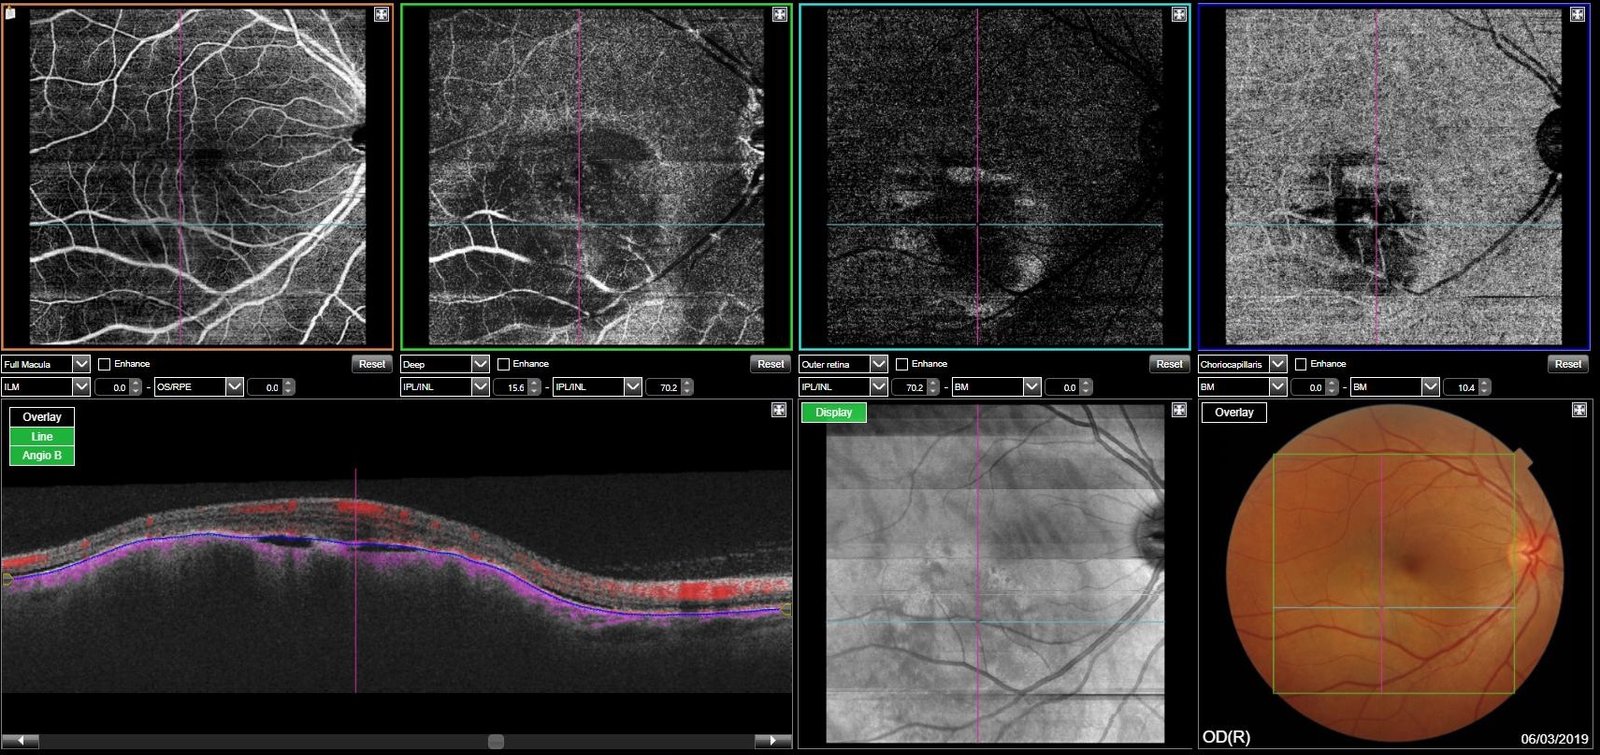

Günümüzde ise bu işlemi son teknolojiler kullanılarak geliştirilen Optik Coherence Anjiyografi(OCTA) sayesinde ilaçsız bir şekilde yapmak mümkündür. Bu yöntemle çok daha kısa sürede (1 dakikadan az), hiçbir yan etki ve alerji riski olmadan, göz dibi damarları üç boyutlu olarak istenilen incelikte ve kesitlerle değerlendirilebilir FFA ile yüzey damarlarını değerlendirilebilmekte iken derin tabakalardaki damarlar hakkında yeterli bilgi edinilememektedir. OCTA ile tüm tabakalardaki damarları (retina ve koroid) net olarak görmek ve değerlendirme yapmak mümkün hale gelmektedir. OCTA aynı zamanda sayısal veriler sağlayarak objektif olarak takiplerde progresyonu ve tedaviye yanıtın değerlendirilmesine imkan verir.

OCTA nın diğer önemli avantajı ise non invaziv bir yöntem olması nedeniyle istenilen sıklıkta tekrar edilebilmesidir. Özellikle yaşa bağlı sarı nokta hastalığı, şekere bağlı göz hastalığı (diyabetik retinopati), göz damarlarının tıkanıklıklarında damar içindeki kan akımının olup olmadığını ve yeni damar oluşumlarını net olarak gösterir. Göz tansiyonu ve göz sinir başının diğer hastalıklarında da önemli bilgiler verir. Sonuç olarak OCTA ilaç yan etkilerine maruz kalmadan göz dibinin dijital olarak görüntülenmesini sağlayan modern bir tanı yöntemidir.